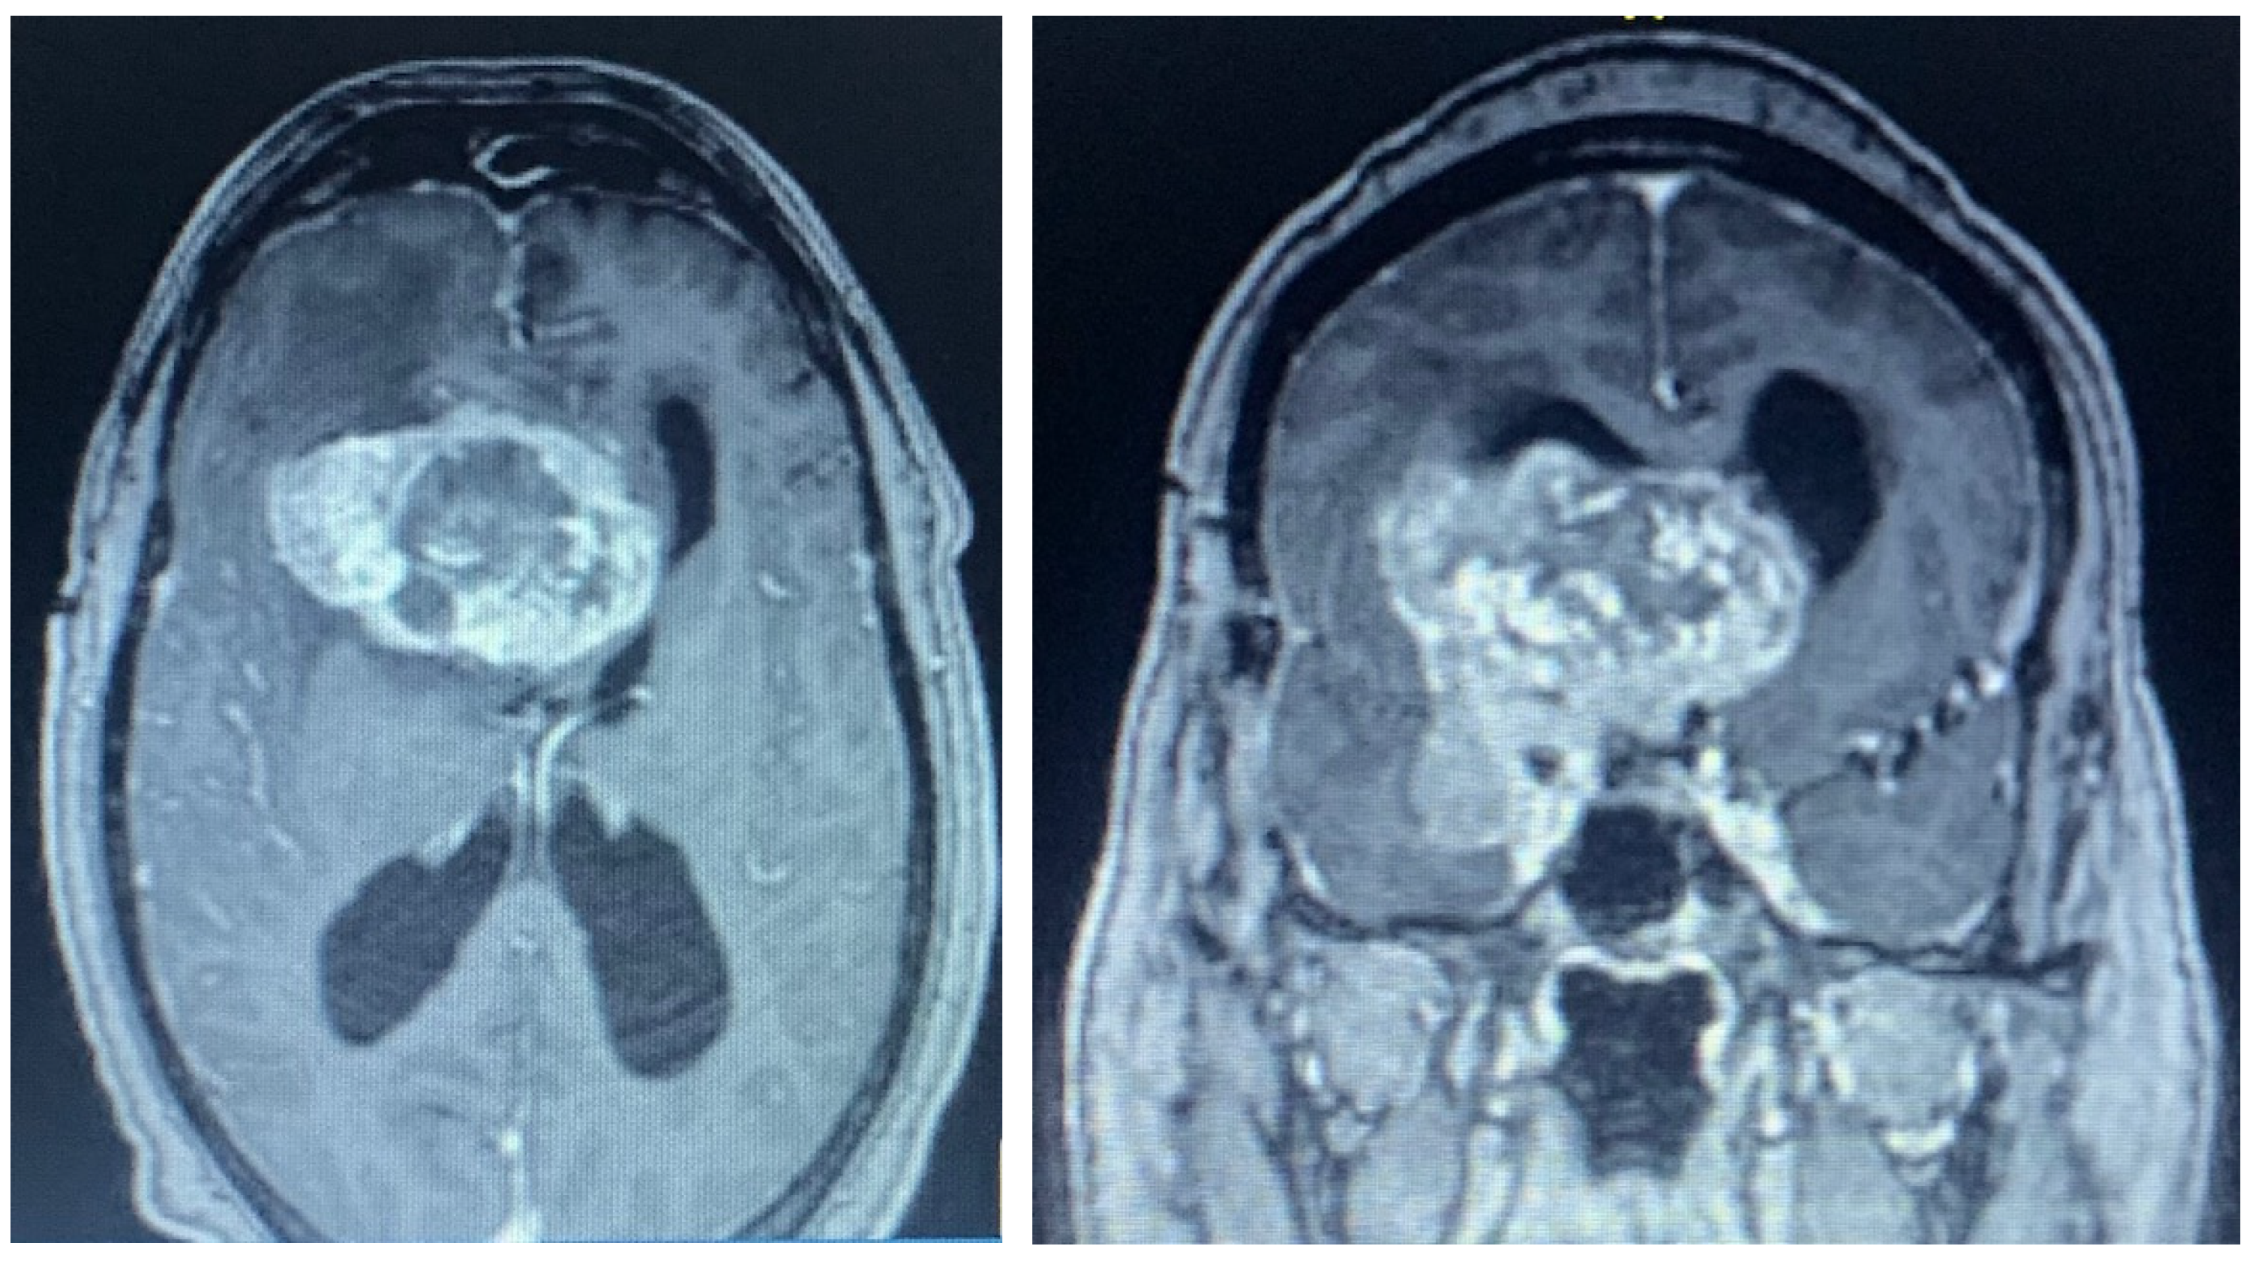

2.1. Case 1

2.2. Case 2